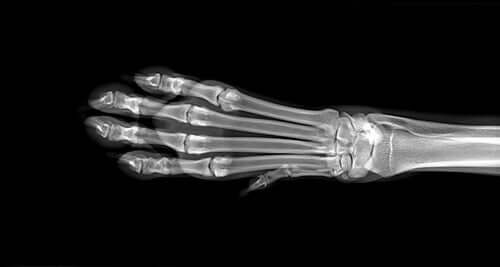

First, your vet will carry out a series of diagnostic tests to identify the cause of the swelling. These will include blood and urine tests and possible x-rays of the limbs. If these tests don’t throw up anything conclusive, they may want to take an MRI scan. If they suspect that it’s osteosarcoma, they’ll perform a bone biopsy.